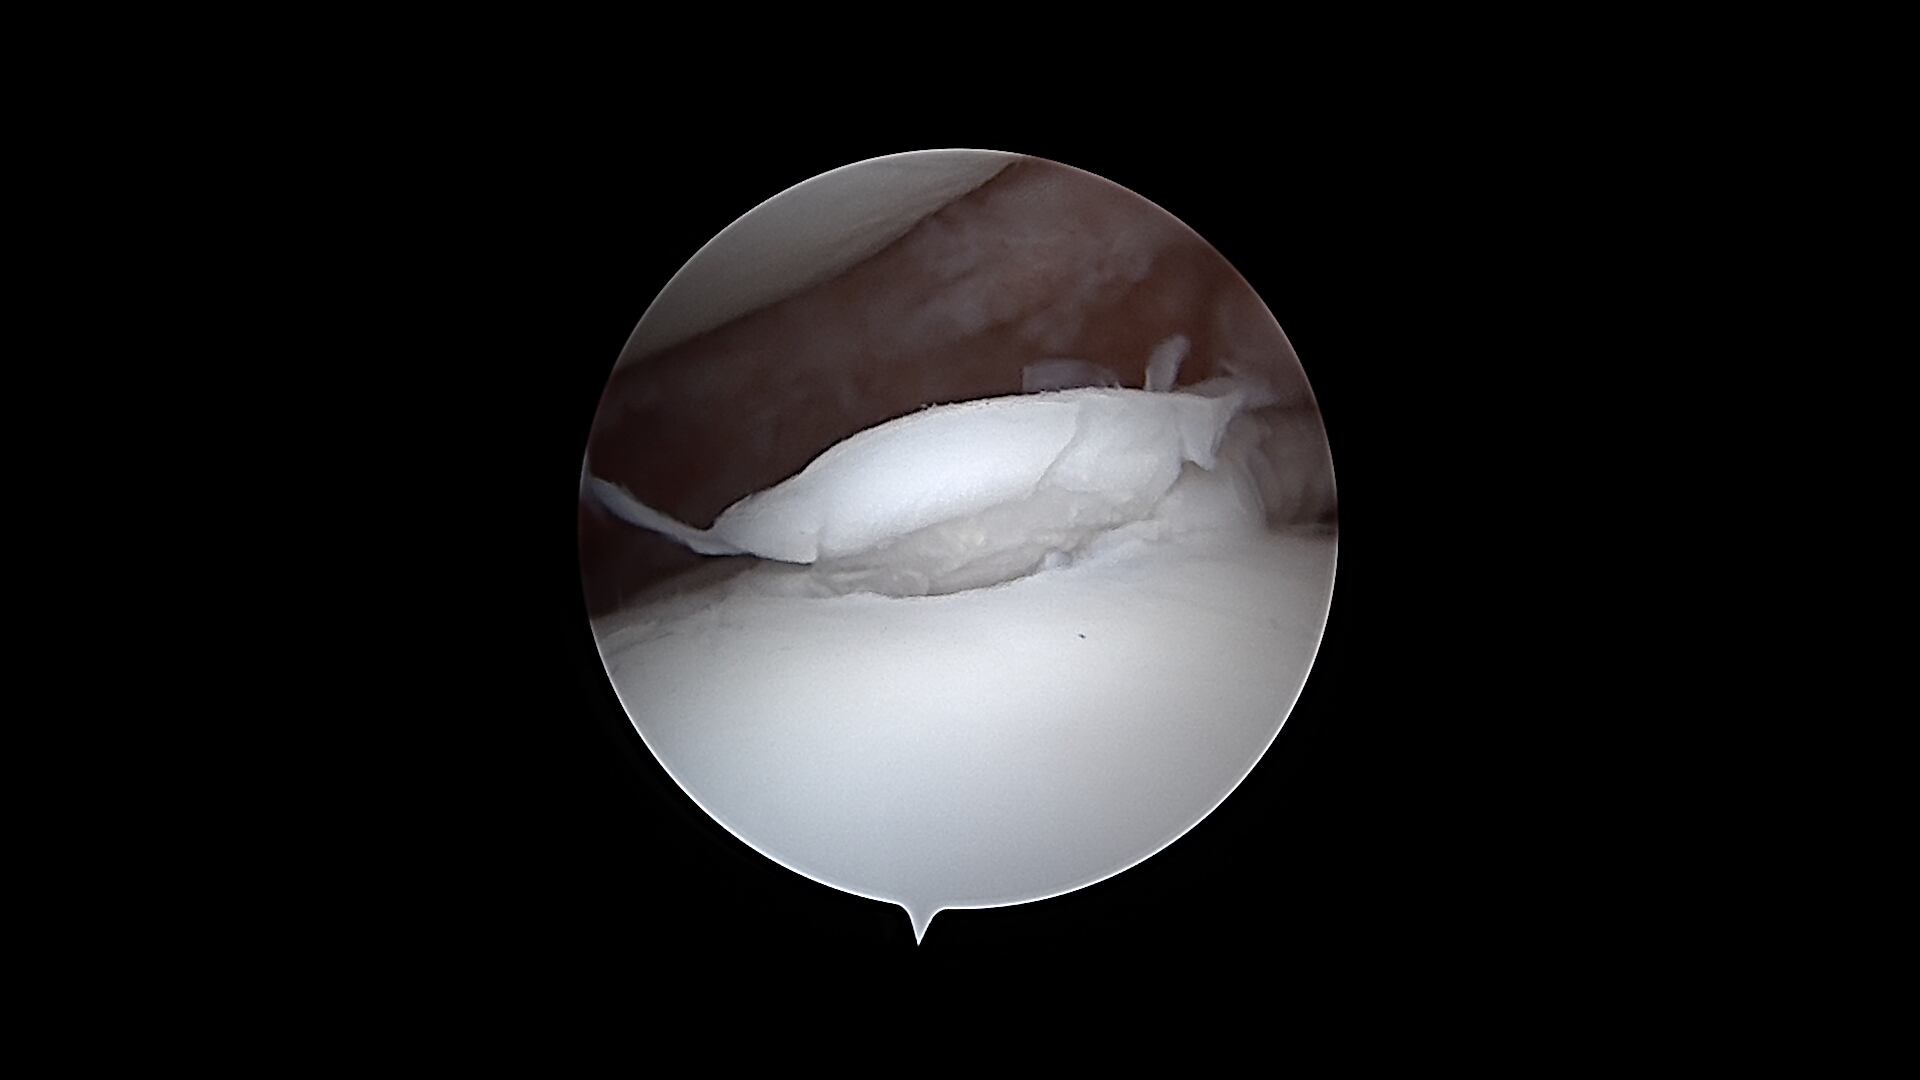

L’arthroscopie de l’épaule est largement utilisée pour le diagnostic et le traitement de l’ostéochondrite disséquante de l’épaule. Cette affection, fréquente chez les jeunes chiens de grande race, se caractérise par une anomalie du cartilage articulaire, le plus souvent localisée sur la face caudale de la tête humérale.

L’arthroscopie permet de confirmer le diagnostic, d’évaluer précisément l’étendue des lésions cartilagineuses et de retirer les fragments instables ou détachés. Elle offre également la possibilité de préparer le lit sous-chondral de manière contrôlée, afin de favoriser un processus de cicatrisation adapté.

Comparée à une chirurgie ouverte, l’arthroscopie de l’épaule est moins invasive, mieux tolérée et associée à des suites opératoires généralement plus simples, tout en offrant une excellente qualité de visualisation et de traitement des lésions.

De gauche à droite : Retrait d’un fragment de processus coronoïde interne sur le coude d’un Cane Corso. Volet d’OCD sur une épaule d’un Border Collie. Exploration du genou d’un Berger Australien : LCP = ligament croisé postérieur, LCA = ligament croisé antérieur.